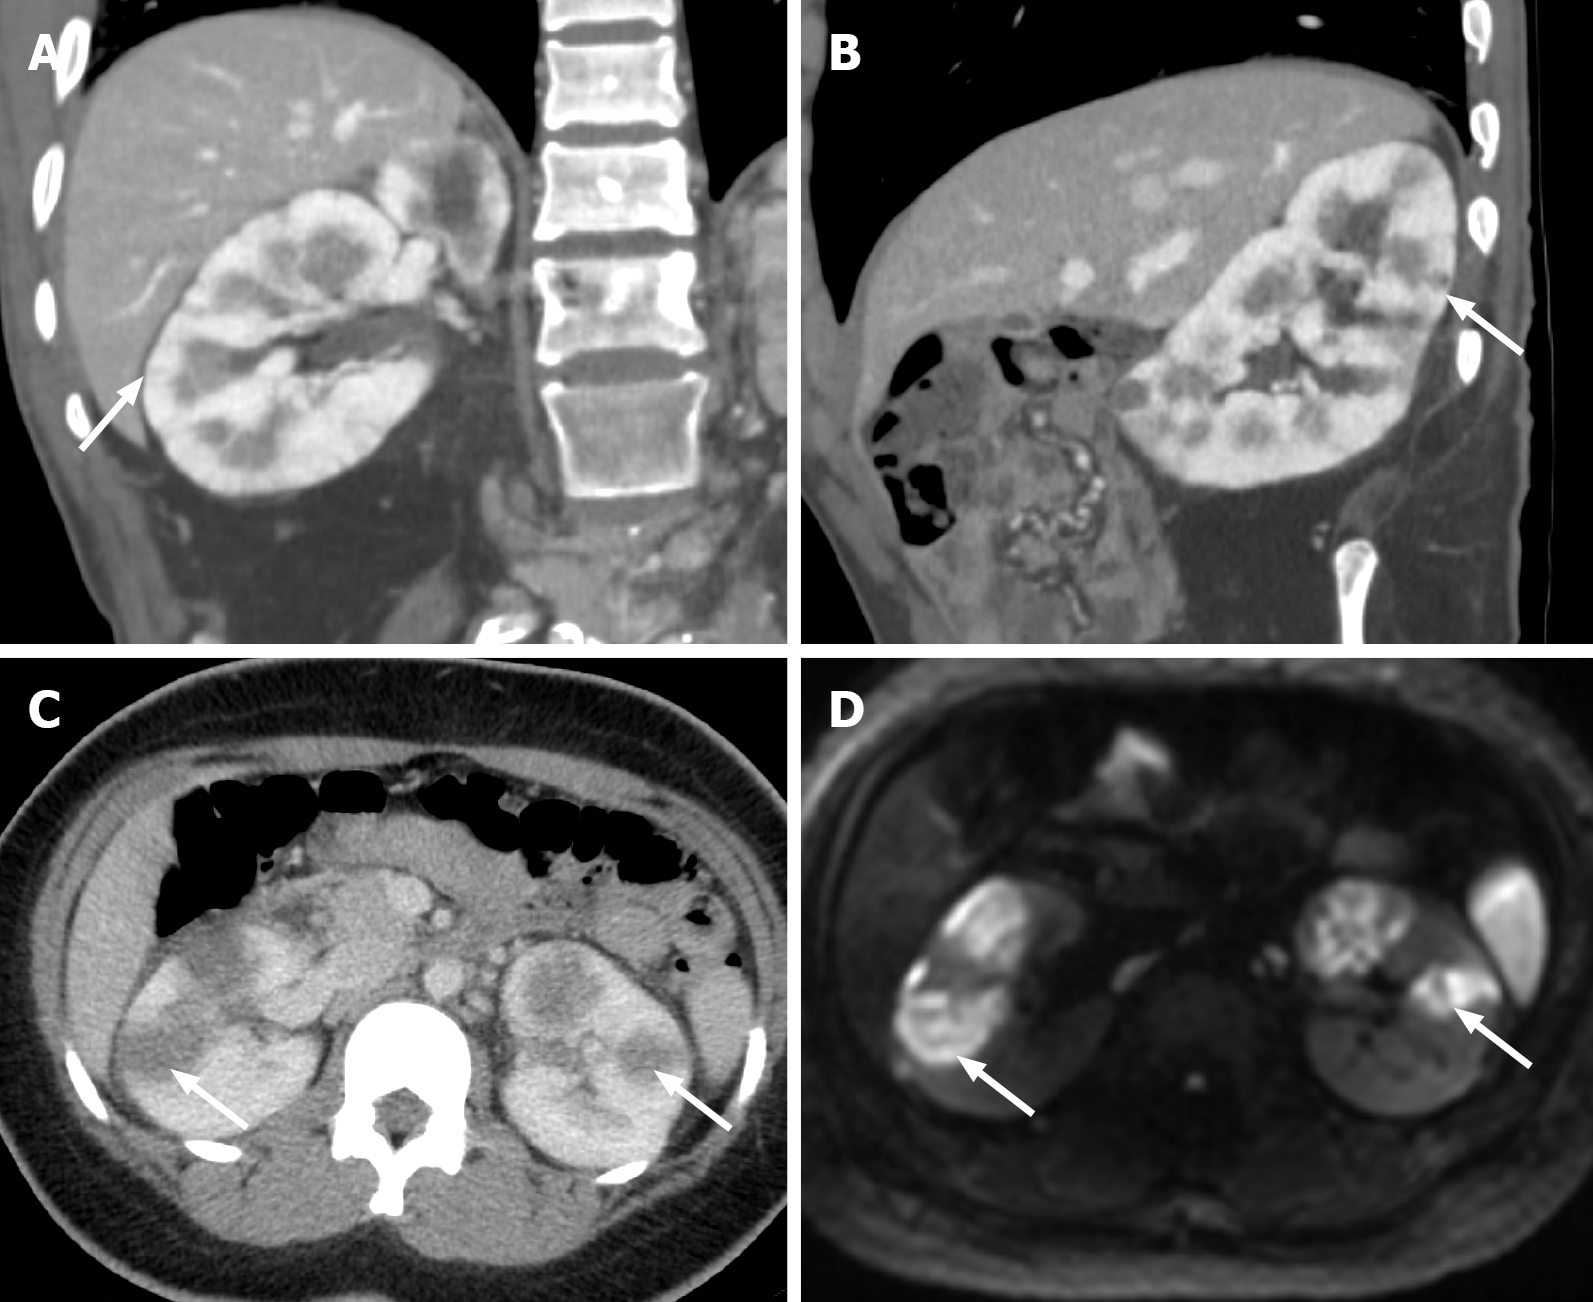

Figure 12 Acute pyelonephritis.

A: Coronal computed tomography in portal venous phase demonstrating striated renal cortical enhancement suggesting acute pyelonephritis (white arrows); B: Sagittal computed tomography in portal venous phase demonstrating striated renal cortical enhancement suggesting acute pyelonephritis (white arrows); C: Axial computed tomography of a different patient with acute pyelonephritis shows multifocal hypoattenuating lesions bilaterally concerning for abscesses (white arrows); D: These findings can be confirmed on magnetic resonance imaging, where the abscesses demonstrate diffusion restriction (indicated by white arrows).